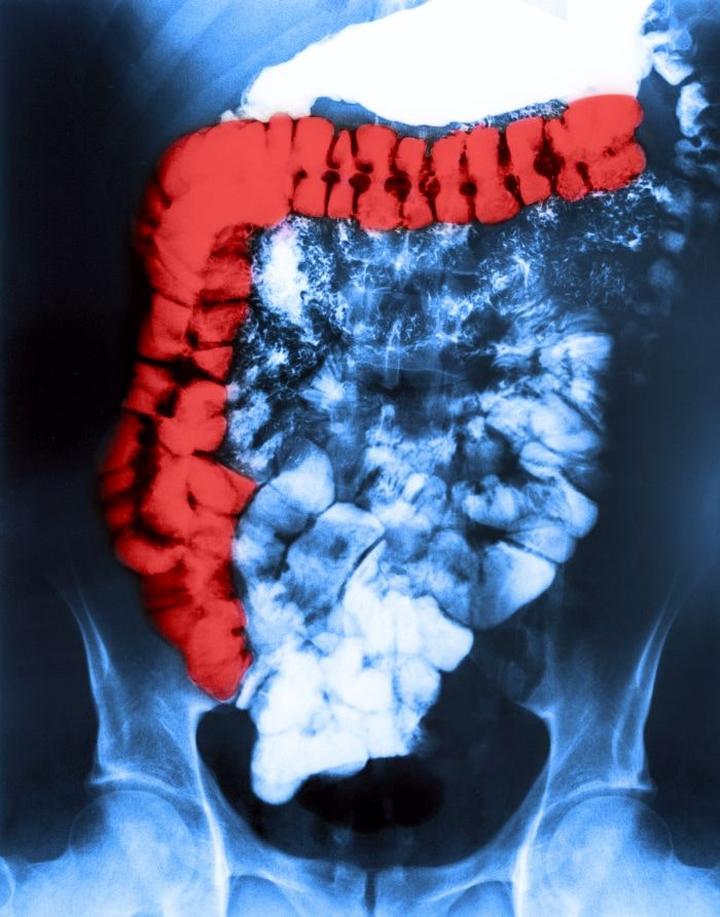

Jeśli należysz do osób z zespołem jelita drażliwego (IBS), to z pewnością zdajesz sobie sprawę, że jedzenie staje się nie tylko przyjemnością, lecz również ryzykowną grą. Każdy kęs może okazać się pułapką! Właśnie dlatego powinieneś wiedzieć, jakich produktów unikać, aby nie kończyć z bolącym brzuchem i zmartwioną miną. Kluczowa zasada dla osób z IBS polega na ograniczeniu lub całkowitym wyeliminowaniu produktów bogatych w FODMAP, czyli fermentujące oligosacharydy, disacharydy, monosacharydy oraz poliole. Dlatego też postaraj się unikać czosnku, cebuli, kapusty, kalafiora oraz roślin strączkowych – ich obecność w diecie to jak zapraszanie grzybów na imprezę, by potem żałować, że zrobili harmider.

Każda osoba z IBS powinna również pamiętać, by nie przesadzać z ilością owoców i warzyw, mimo że są one zdrowe. Piękne kolory i kuszące smaki nie mogą cię zwieść – zjedzenie dużej ilości surowych owoców i warzyw może prowadzić do poważnych problemów żołądkowych. W tej grupie szczególnie unikaj strączków, suchych śliwek oraz produktów mlecznych. Zamiast tradycyjnego mleka krowiego, zdecyduj się na coś na bazie migdałów – i nie, nie chodzi tu o studzenie emocji.

Rola błonnika w zespole jelita drażliwego zasługuje na naszą uwagę, ponieważ dla wielu osób z IBS (zespołem jelita drażliwego) staje się on nie tylko wyzwaniem dietetycznym, ale również codziennym dylematem. Błonnik przypomina znaną paczkę z napisem „musisz go spróbować” – choć nie zawsze jesteśmy pewni, czy go chcemy, skryta wątpliwość sugeruje, że działanie to nie zaszkodzi. Warto jednak zauważyć, że nie wszystkie rodzaje błonnika mają tę samą moc. Dlatego dobrze jest przyjrzeć się, co może nasilać objawy tej dolegliwości; w końcu nikt z nas nie pragnie wzdęć i bólów brzucha w codziennym życiu, prawda?

W diecie osób z IBS błonnik rozpuszczalny pełni kluczową rolę, dlatego powinniśmy traktować go jak najlepszego przyjaciela. Spotykamy go m.in. w owocach takich jak banany oraz w płatkach owsianych. Z kolei błonnik nierozpuszczalny, który ukrywa się w surowych warzywach oraz pełnoziarnistych produktach, takich jak chleby czy włókniste potrawy nabiałowe, może okazać się naszym wrogiem. Osoby z biegunką mogą odczuwać dyskomfort po jego nadmiarze, a ponadto lamentować z powodu kurczów brzucha, co z pewnością nie sprzyja dobremu nastrojowi ani przyjemnej atmosferze. To klasyczny paradoks tej znanej substancji!